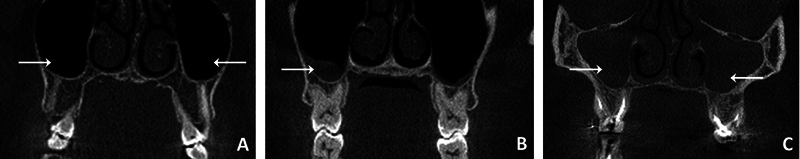

Introduction  In the literature, there is divergence about the relationship between anatomical variations of the turbinates and nasal septum (NS) and alterations in the maxillary sinus (MS) mucosa. Objective  To determine, through cone-beam computed tomography (CBCT) images of Brazilian individuals, the prevalence and relationship of anatomical variations of the turbinates and NS with alterations in the mucosa of the MS, as well as to analyze the relationships of these variables with demographic data. Methods  The present cross-sectional study involved the analysis of 120 CBCT scans using the i-CAT Vision software, conducted by 2 calibrated examiners. The MS, lower and medium turbinates, and NS were evaluated. Data on gender, age, and the side affected by anatomical variation were also collected. The intra- and interexaminer agreements were assessed using Kappa indices. The association was analyzed using the Chi-squared or Fisher exact tests, and measured by the Phi, Cramer V, or Kendall Tau-C values. Results  Most patients presented partial opacification of the MS (89.2%), inferior turbinate hypertrophy (TH) (60.8%), and NS deviation (85%). There were no cases of inferior concha bullosa (CB), while the prevalence of middle CB was of 20%. Variation in the turbinates, CB, and NS were not significantly related to changes in the MS mucosa. Conclusion  We can conclude that, in the evaluated sample, there was no significant associations involving the studied variables.